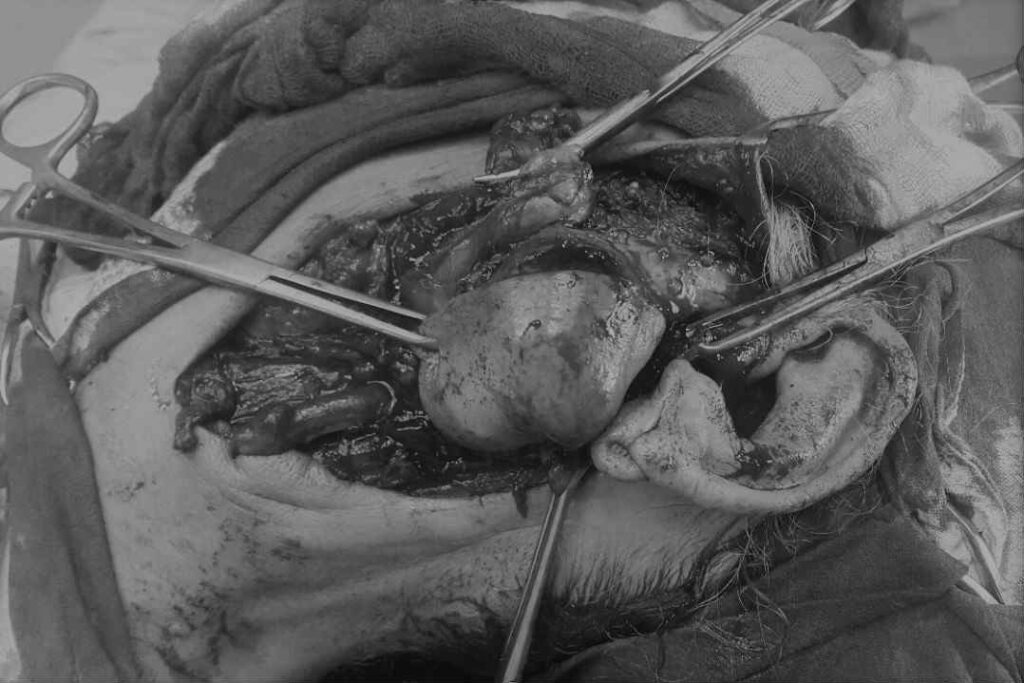

عملية استئصال ورم عملاق من البطن

عملية استئصال ناجحة لورم كبير في البطن